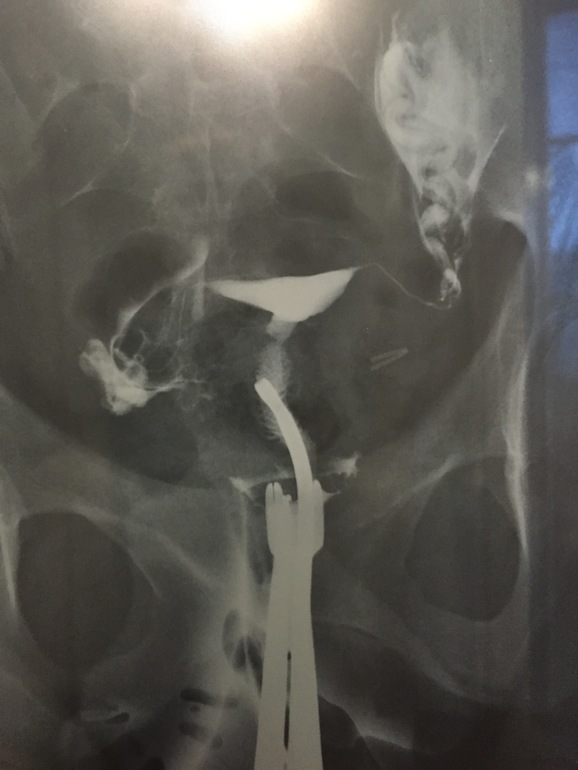

Здравствуйте! Мне 21 год, мужчина. У меня такая ситуация. 17 числа мне делали небольшую операцию на позвоночнике и ставили катетер в мочевой пузырь на несколько часов. Через три дня я уже был дома и все было хорошо, эрекция была нормальная и сперма вроде тоже нормальная, но примерно 26 числа заметил что сперма стала немного розовато-оранжевая и семяизвержение было каким то вялым (болей не было, но сильно удовольствия не было тоже). Впоследствии, вот уже 4 дня, как моя мочеполовая система какая-то вялая (если раньше эрекция могла наступать случайно и естественно в течение дня, то сейчас такого не происходит). Ощущение как будто мой член "устал и ушел в отпуск".

Но больше всего меня беспокоит конечно же розовато оранжевый оттенок спермы.

Не знаю связано ли с этим, у меня по вечерам температура до 37.7 поднимается (4 дня).

Вам конечно же нужно пройти хотя бы минимальное обследование. Похоже у вас осложненный уретрит, простатит и везикулит.( я опираюсь на ваши субъективные ощущения. Если есть возможность пройдите безотлагательно УЗИ простаты, сдайте мочу на анализ и если можно мочу на флору. Если вам некому обратиться, напишите мне на почту.